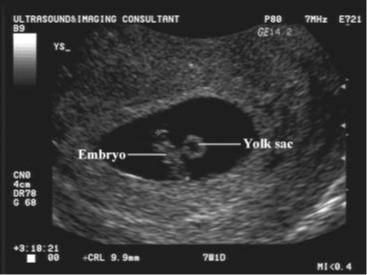

شكل الجنين الأسبوع السابع من الحمل بالسونار

قد تظنين أن حملك في مرحلة مبكرة للغاية، وأن الجنين في الأسبوع السابع لا يزال صغيرًا ولا يمر بأي تطورات، والحقيقة أن الجنين قد ازداد حجمه الآن ويبلغ طوله ما بين تسعة إلى عشرة ملليمترات، وهو أكبر بـ 10000 مرة مما كان عليه عند أول الحمل، تتشكل أصابع يدي وقدمي طفلك الآن، على الرغم من عدم انفصالهما تمامًا عن الجسم.

مع ذلك، فإن معظم هذه التفاصيل لن تتمكني من رؤيتها على شاشة السونار، إذ يكون الجنين صغيرًا جدًا فلا يمكنكِ رؤية التفاصيل، ولكن سيمكنكِ سماع صوت دقات قلبه، وسوف ترين الشكل العام وبالطبع لن يشبه شكل الجنين المميز، أما التطورات التي يمكن رؤيتها تشمل:

- كيس الحمل: هذه واحدة من أولى العلامات المرئية للحمل، وهي تشير إلى المساحة المليئة بالسوائل المحيطة بالجنين، عادةً ما يتكون في غضون خمسة أسابيع من الحمل، ويبدو شكله دائريًا داكنًا أو مستطيلًا.

- كيس الصفار أو المح: حتى قبل أن تتمكني من رؤية الجنين داخل كيس الحمل يمكن رؤية كيس المح، وهو أول شيء ينمو داخل كيس الحمل ليمد طفلك بالعناصر الغذائية والأكسجين حتى تتطور المشيمة، سيبدو مثل حلقة بيضاء صغيرة أو فقاعة داخل الكيس.

- القطب الجنيني: هذا أول مؤشر على أن طفلك يتشكل داخل كيس الحمل، سيبدو شكلًا سميكًا مائلًا إلى البياض مرتبطًا بكيس الصفار، قد يكون منحنيًا أو مستطيلًا، يمكن عادةً اكتشافه خلال الأسبوع السادس من الحمل باستخدام الموجات فوق الصوتية عبر المهبل.